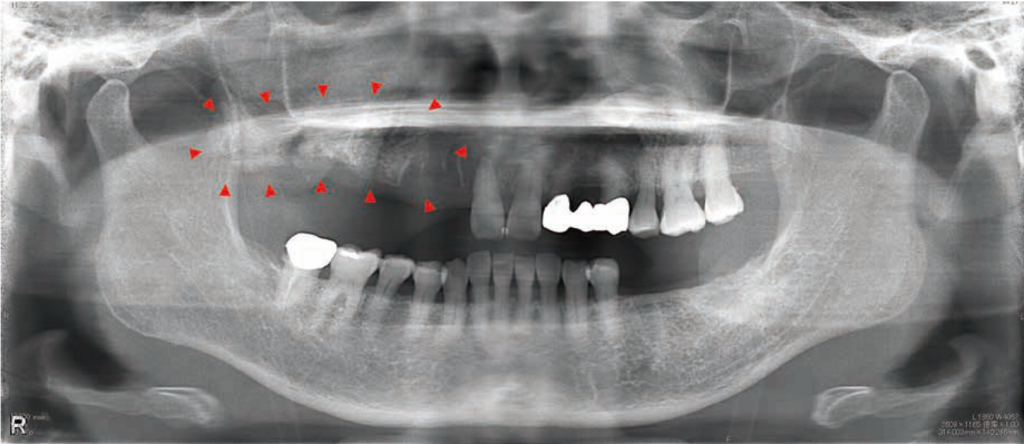

初診時:パノラマX線写真

上顎右側前歯部から臼歯部にかけての骨硬化像ならびに右側上顎洞に陰影を認めた。

初診時:単純CT画像

右側上顎洞内には陰影を認め、上顎右側前歯部から臼歯部にかけての腐骨様組織を認めた。